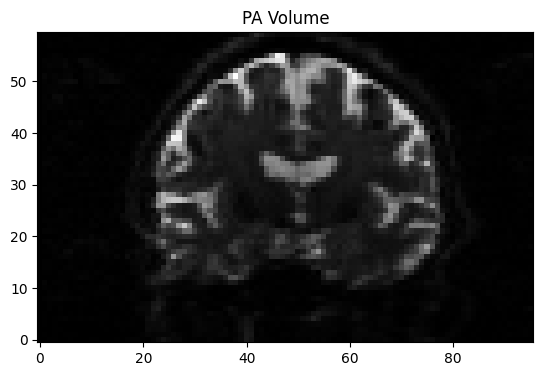

img = nib.load("AP_PA.nii.gz")

data = img.get_fdata()

mid_slice = data.shape[1] // 2 # middle sagittal slice

for i in range(10): # flip 10 times between AP and PA volume

for vol in range(2):

plt.imshow(data[:, mid_slice, :, vol].T, cmap='gray', origin='lower')

plt.title(f"{'AP' if vol == 0 else 'PA'} Volume")

display(plt.gcf())

time.sleep(1.0) # flip every second

clear_output(wait=True)